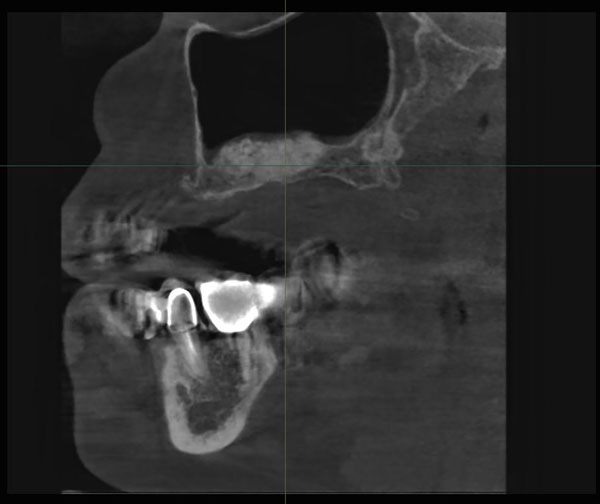

Bone Density - плотность костной ткани вокруг спозиционированного имплантата играет огромную роль при подготовке к оперативному вмешательству. По шкале Хаунсфилд (HU) в программном обеспечении врач определяет точные параметры плотности костной структуры, интересующей зоны (Рис.3).

Рис.3 Программное обеспечение Ez3D-i. Дентальная объемная томограмма. Определение плотности остеопластического материала при планировании имплантации через 6 месяцев после операции синус-лифтинг